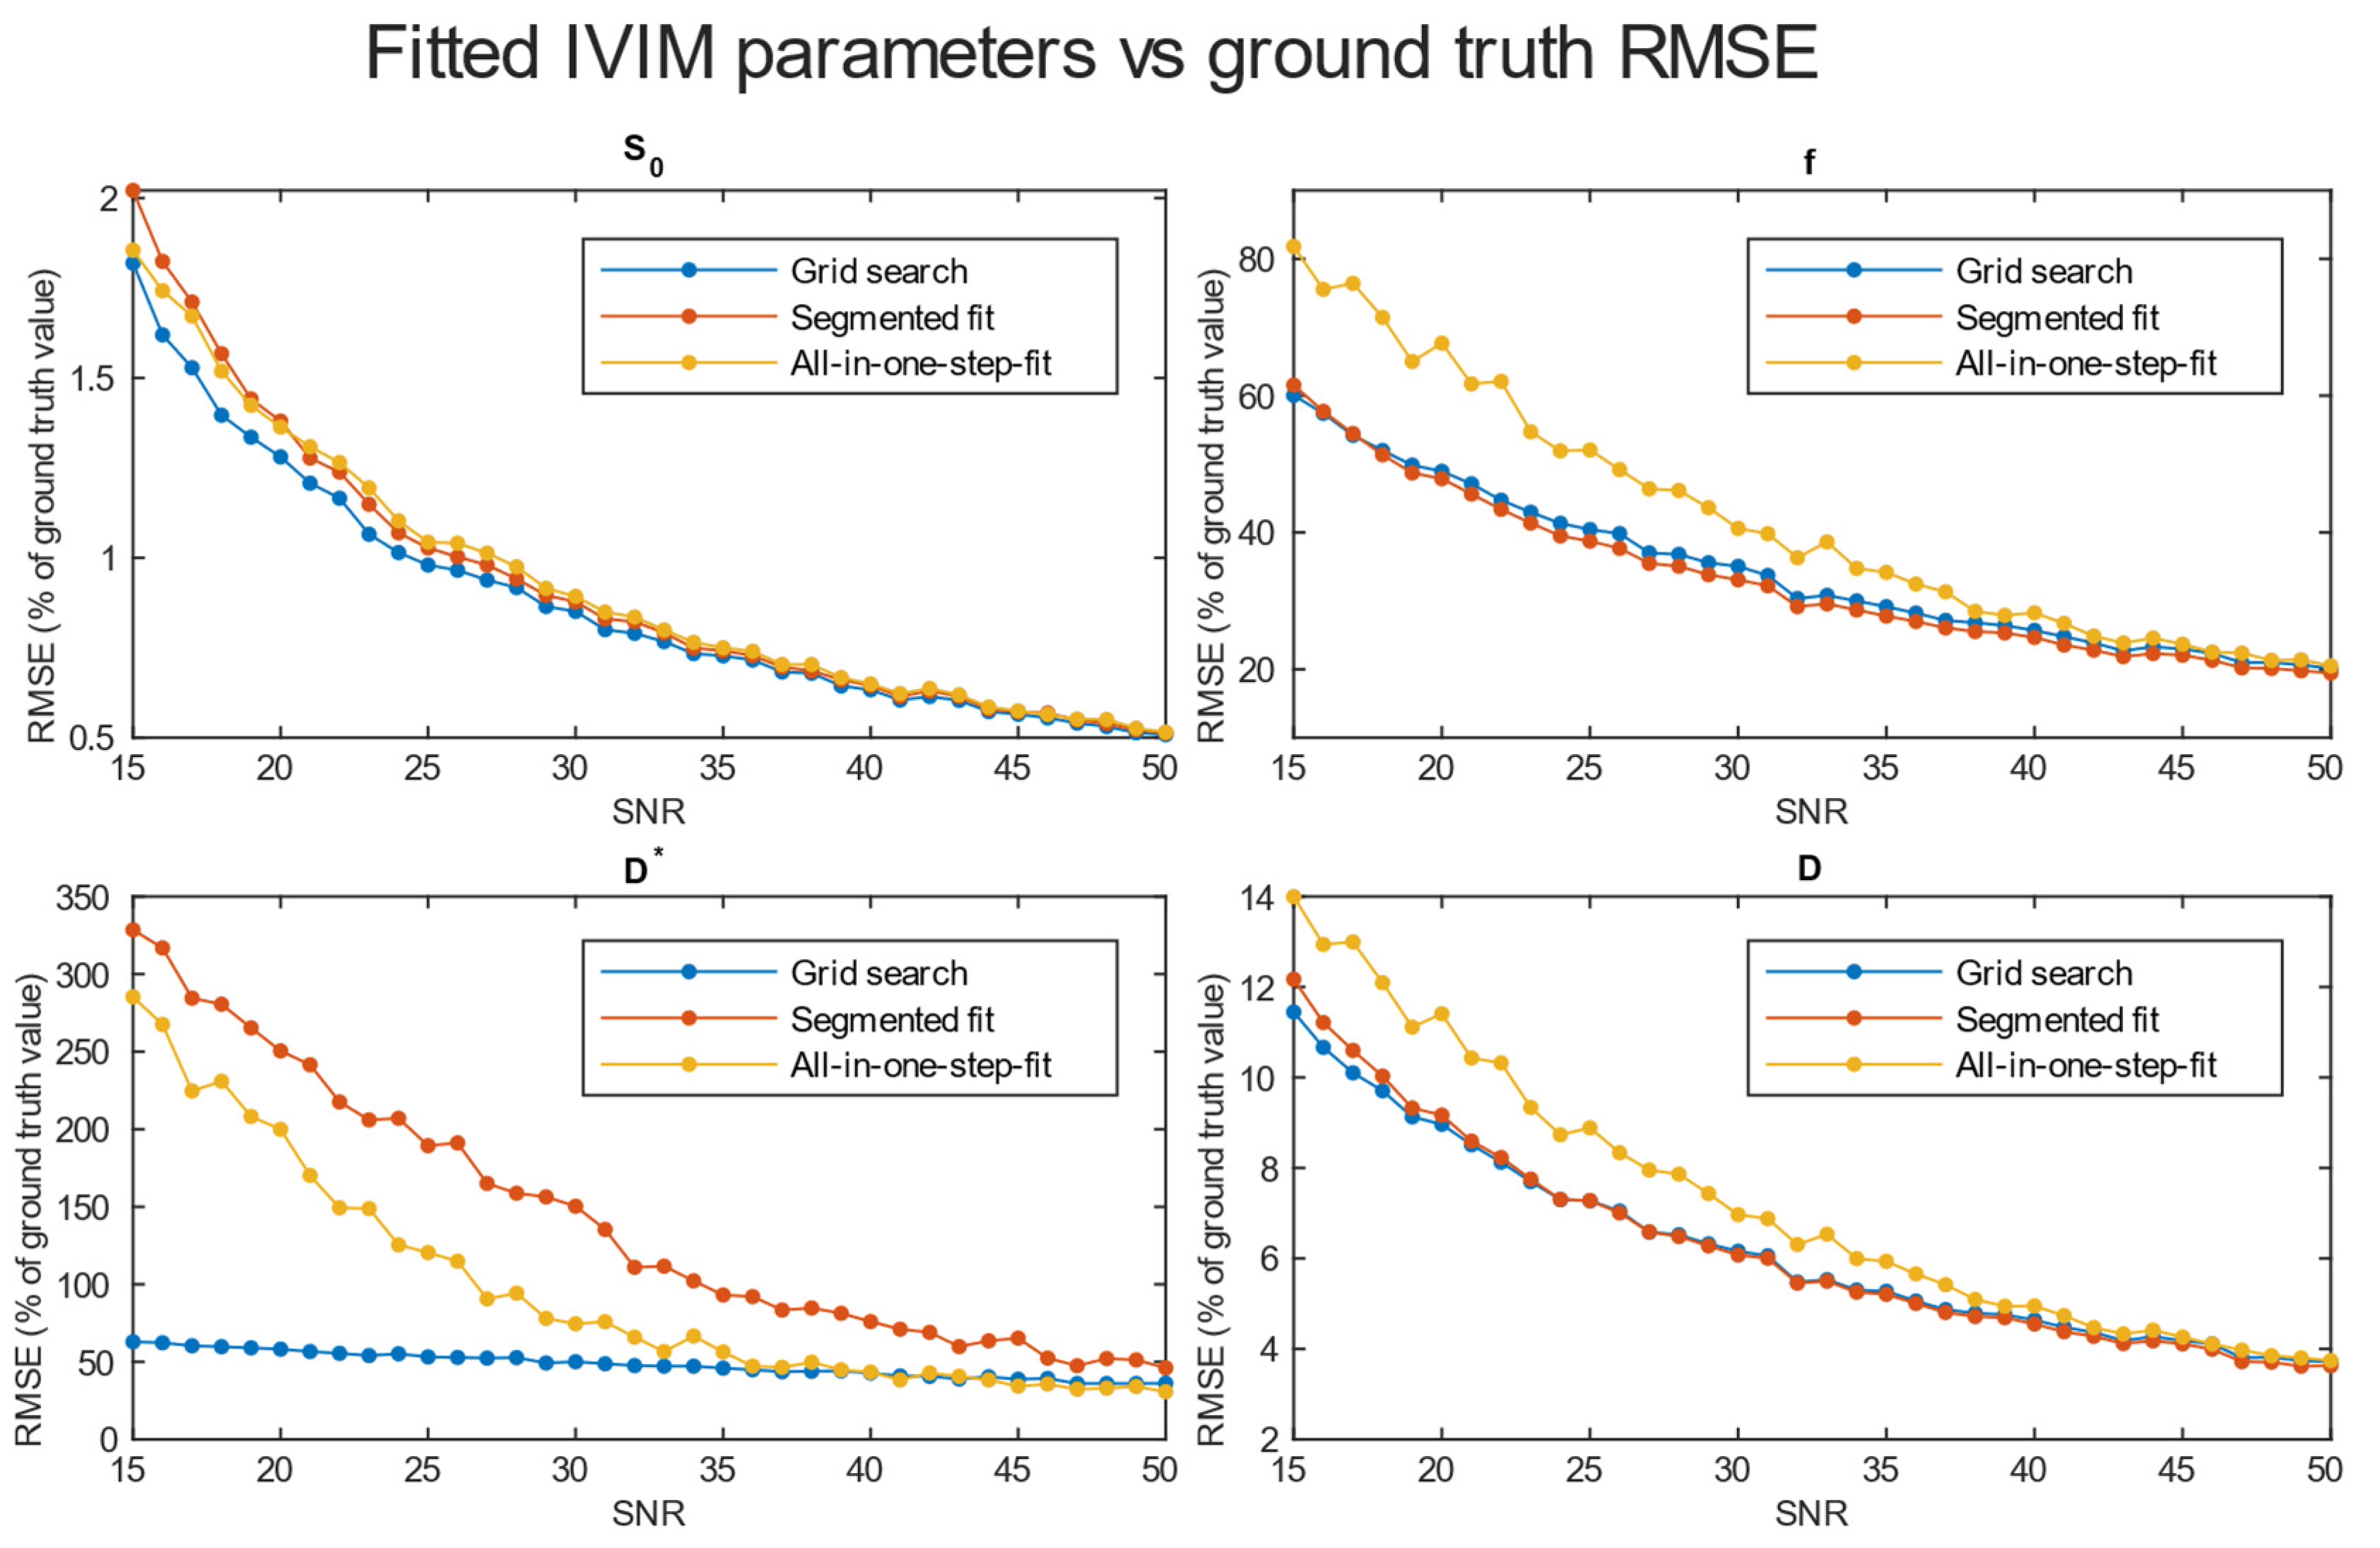

3.2. Evaluation of Accuracy